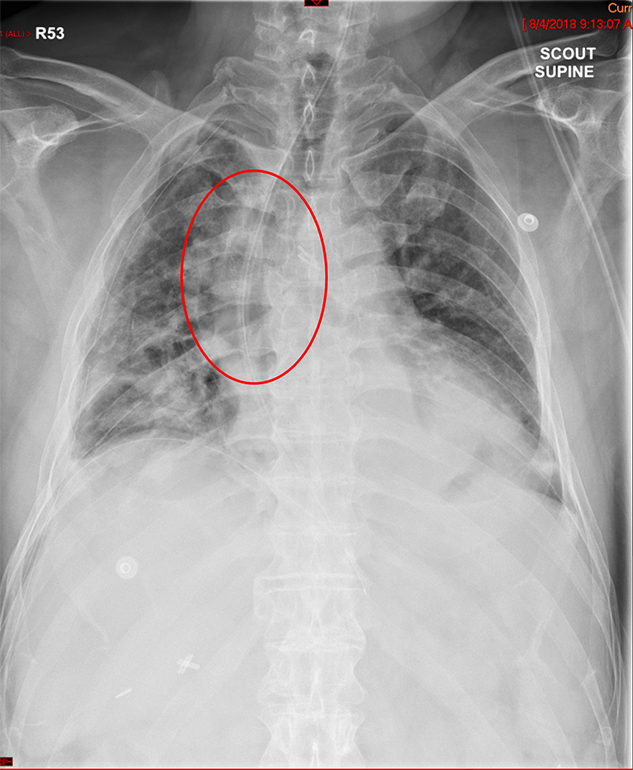

- The technologist will obtain a scout radiograph(s) to include the chest and upper abdomen to determine the location of the surgical chain sutures or surgical staples

(key image 1).

- The esophagogastric anastomosis is usually located at the level of the aortic arch or just below it.